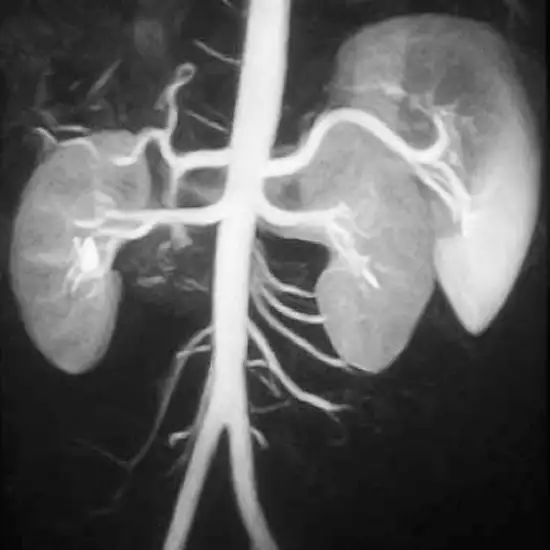

This test helps to capture the images of veins in the abdomen to evaluate considerable abnormalities like arterial feeding of hepatocellular carcinoma, the encasement of arteries and segmental portal thrombosis in pancreatic carcinoma.

MRA abdomen angiography procedure is the diagnostic imaging technique that uses magnetism and radio waves to  produce scan images of the abdominal vessels for detecting and diagnosing certain hepatocellular or other vessel problems such as portal thrombosis in pancreatic carcinoma.

Doctors use the magnetic resonance abdomen angiography scan to diagnose different types of vascular diseases occurring in the abdomen with the help of scan images produced. It can help detect conditions such as atherosclerosis, blood clots, and others.

The MR abdomen angiography test is a non-invasive, safe, and accurate diagnostic test with a sensitivity and specificity of 97% and 93% respectively. The test can help detect any vascular disease or problems with adequate accuracy.